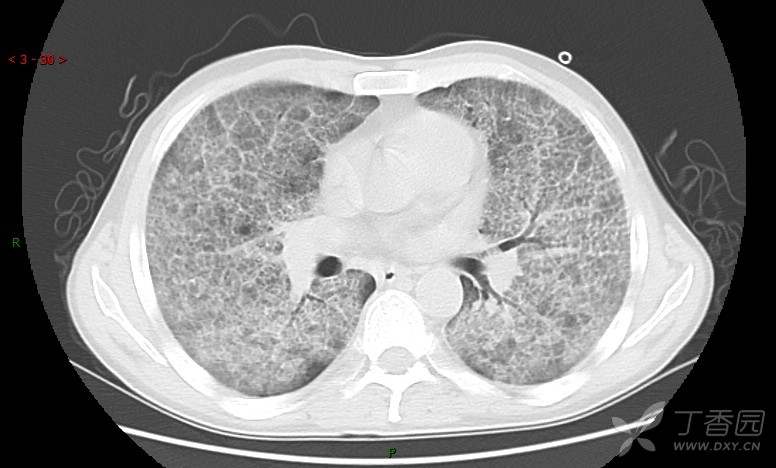

地图+铺路石征=PAP?那升高的CEA怎么说(病例3连发,附其他2例链接)

患者男,42岁,咳嗽半年余,加重伴憋喘2月余。

患者半年余前无明显诱因出现间断咳嗽,干咳为主,偶咳少量黄白痰,剧烈咳嗽或运动后可出现轻度憋喘,无高热、脓臭痰,无胸痛、咯血及晕厥,无低热乏力及盗汗,无心前区压榨感及夜间阵发性呼吸困难,初未在意,未予正规诊治。2月余前患者自觉上述症状较前加重,咳嗽、憋喘明显,黄白色粘痰略有增多,伴有发热,热前伴有畏寒、寒战,体温最高达38.9℃,先后就诊多家医院,入住重症监护室,未行气管插管,考虑“重症肺炎”,给予“美罗培南、复方磺胺甲噁唑”等药物抗感染,“卡泊芬净”抗真菌,并给予“甲泼尼龙”等药物治疗35天,经治疗后症状好转于2018-04-02出院。患者自出院后仅应用中药治疗(具体不详),并给予家庭氧疗,平素仍有间断咳嗽,咳少量黄白色粘痰,活动后憋喘明显,活动耐量差,以卧床为主。